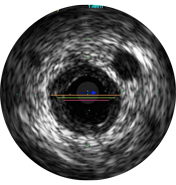

Vessel diameters may be determined at proximal and distal reference sites by obtaining lumen diameters, mid-wall diameters (halfway between lumen and vessel), or vessel diameters, in order of increasing aggressiveness.

If maximum and minimum diameters are used, measurements should bisect the geometric center of the vessel rather than the center of the IVUS catheter.